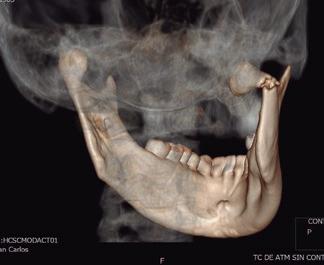

dolor y limitación de los movimientos mandibulares. Para ello, se hará un abordaje extraoral y se refracturará la original o se completará una nueva osteotomía, generalmente con sierras mecánicas o bisturíes piezoeléctricos, reposicionando el fragmento mal colocado y estabilizándolo en el lugar correcto. Estas cirugías secundarias suelen ser más complicadas que las primarias, sobre todo por los tejidos blandos que se adaptan a la malposición previa ocupando el espacio original y son difíciles de retirar. Un caso muy evidente es la ATM, donde tras una fractura condilar mal colocada con desplazamiento del cóndilo antero-medialmente se produce un espacio intraarticular, que es ocupado por una hipertrofia de los tejidos blandos articulares y que dificulta la reposición adecuada. En estos casos es especialmente necesario realizar un buen estudio de imagen, sobre todo con TC y algunas veces con RM, para evaluar la posición de los fragmentos y de los tejidos blandos, siendo muy recomendables los estudios TC-3D (fig. 1). Si se sospecha una pseudoartrosis por una necrosis ósea o una mala vascularización, puede ser útil una gammagrafía ósea con Tc99 o un SPECT-TAC que evalúe la irrigación de la zona. Una vez se ha decidido la necesidad de un abordaje abierto, se deben valorar dos cosas importantes: la incisión-abordaje necesaria y el material de osteosíntesis ideal para tratar la fractura.

SFIG. 1, a-e. Fractura subcondílea derecha tipo V de Spiessl en una paciente joven tras un accidente doméstico. a) OPG preoperatoria donde se aprecia la línea de fractura subcondilar derecha con desplazamiento fragmentario (flecha roja) y el movimiento de dislocación ántero-medial que ha realizado el fragmento condilar (flecha amarilla); la paciente había sufrido una fractura orbitaria hacía unos años, observándose una miniplaca de titanio colocada en el reborde infraorbitario izquierdo. b) Corte axial y densidad hueso de la TC con el fragmento condilar dislocado adelante hacia medial muy cercano a la apófisis pterigoides (flecha verde) aunque con aparente contacto entre fragmentos (flecha roja). c) Corte coronal de la TC con el desplazamiento entre fragmentos (flecha roja) y la dislocación hacia medial (flecha amarilla) fuera de la fosa glenoidea (puntos verdes). d) Vista anterior de la reconstrucción 3D con sustracción de estructuras de la TC en la misma fractura. e) Vista póstero-lateral de la misma reconstrucción; estas imágenes son muy útiles durante la cirugía para apreciar los movimientos en los tres planos del espacio que realizó el fragmento condilar, aunque solamente informa de las estructuras óseas y no de los tejidos blandos.